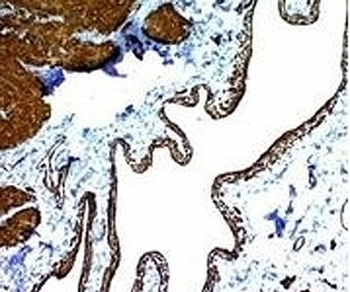

IHC: Formalin-fixed, paraffin-embedded Leiomyosarcoma stained with Smooth Muscle Actin antibody (clone SPM332).